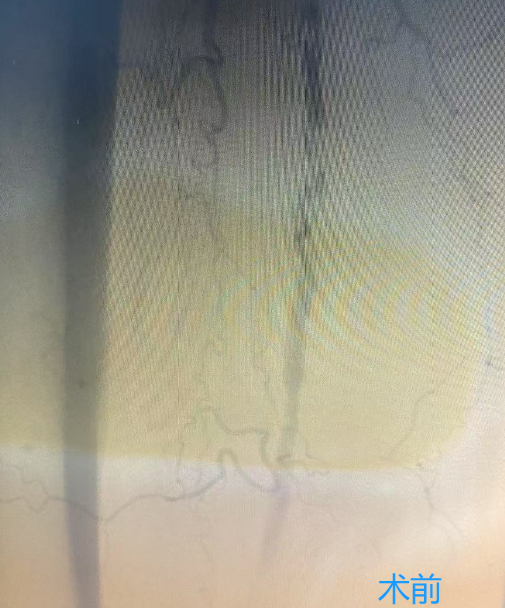

下肢动脉硬化闭塞症的治疗方式包括:生活方式调整、药物治疗、血管腔内治疗、外科手术和康复等方法,可有效缓解症状,提升生活质量。特别是下肢动脉旋切术,作为微创技术,能有效清除血管壁上的斑块。

葫芦岛市第二人民医院血管介入病区现已常规开展下肢动脉旋切术,标志着我市周围血管疾病微创技术及相关领域诊疗水平迈上了新台阶。这一技术的广泛应用,结合先进的影像技术,将为更多下肢动脉疾病患者带来福音,让他们重获健康与希望。